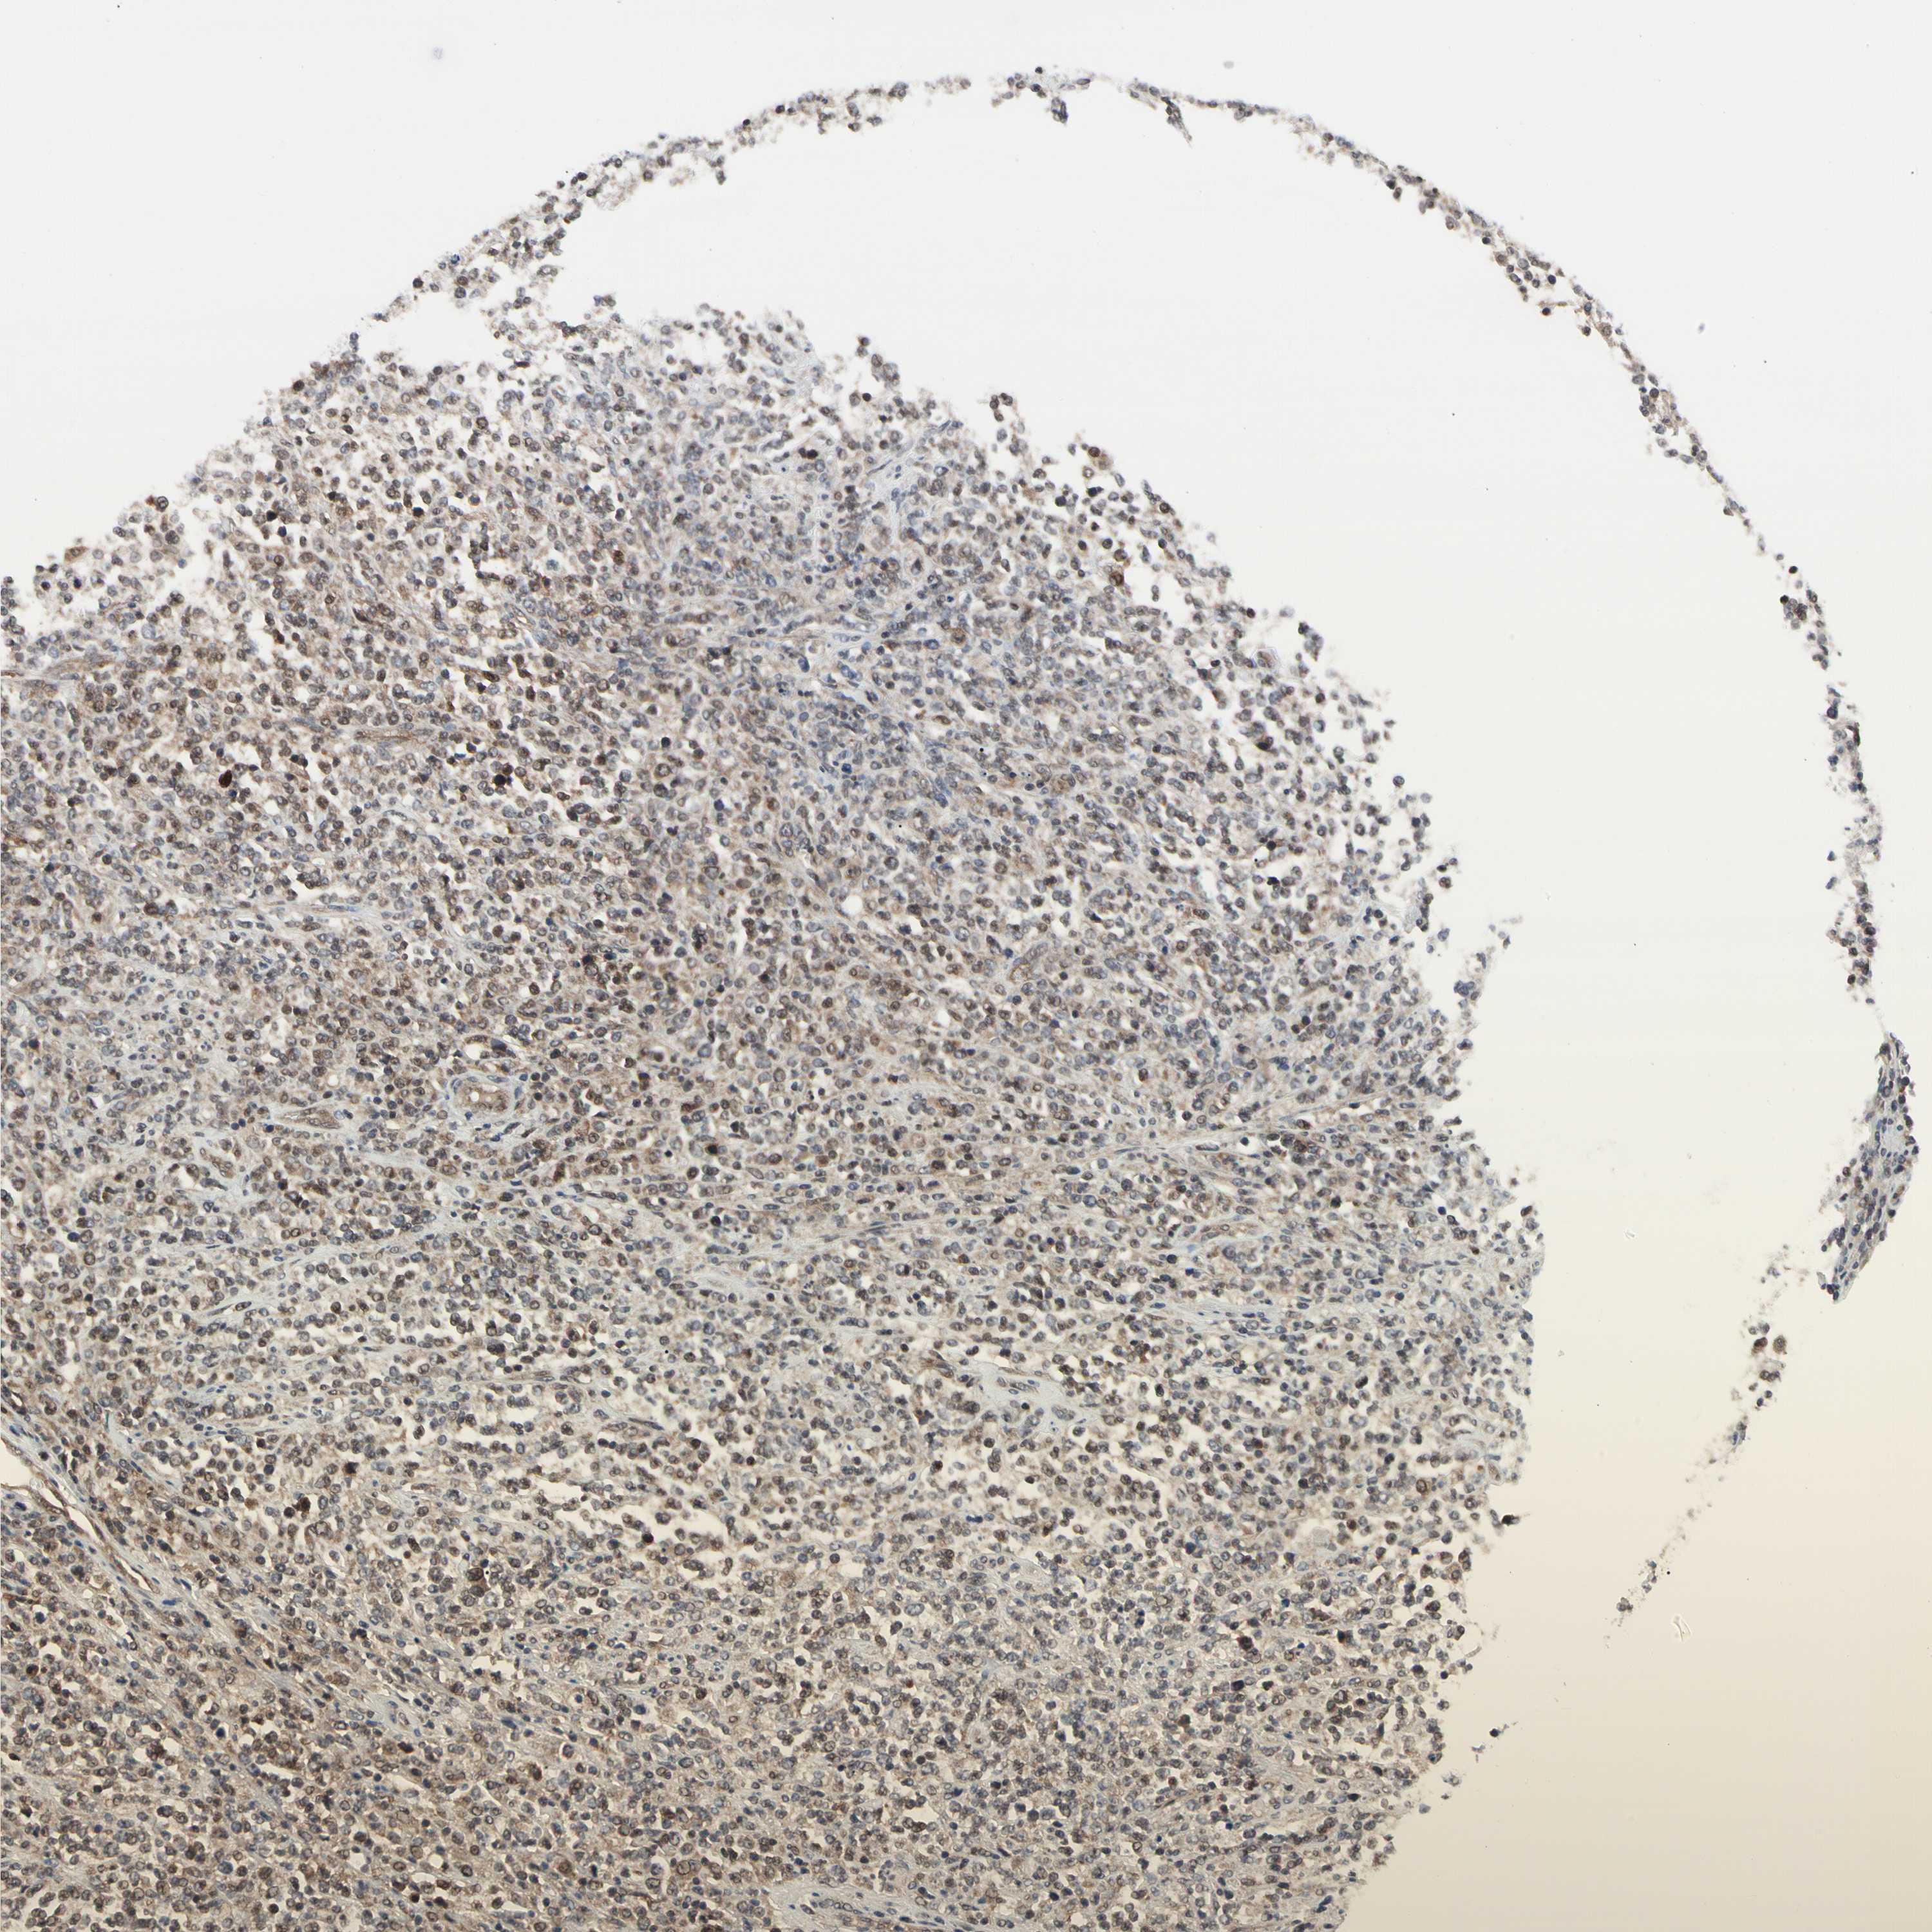

LYMPHOMA - Protein expressioni

A mouse-over function shows sample information and annotation data. Click on an image to view it in a full screen mode. Samples can be filtered based on level of antibody staining by selecting one or several of the following categories: high, medium, low and not detected. The assay and annotation is described here.

Antibody staining in the annotated cell types in the current human tissue is reported as not detected, low, medium, or high, based on conventional immunohistochemistry profiling in selected tissues. This score is based on the combination of the staining intensity and fraction of stained cells.

Each image is clickable and will lead to virtual microscopy that enables deeper exploration of all samples and also displays staining intensity scores, fraction scores and subcellular localization as well as patient and tissue information for each sample.

Antibody HPA064535

Staining

High

Medium

Low

Not detected

Intensity

Strong

Moderate

Weak

Negative

Quantity

>75%

75%-25%

<25%

None

Location

Nuclear

Cytoplasmic/membranous

Cytoplasmic/membranous,nuclear

Malignant lymphoma, non-Hodgkin's type, Low grade